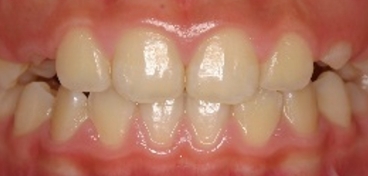

しかし当院の歯並びもよく観察すると、少しは指数が増加、つまり多少は歯並びが悪くなっていることが分かります。実はこれは自然な歯並びの変化と同じものである事がわかりました。つまり歯並びは下の写真が示すように矯正をしてない人でも、変化するのです。その自然な変化をリトル教授のお仲間のシンクレア先生が報告しており、そのデータを追加したのが下の図です(グラフのグレー)。これをみると元々綺麗な歯並びだったものも7年経過するとリトルの指数が35%も増加していることが分かります。

自然な歯の移動